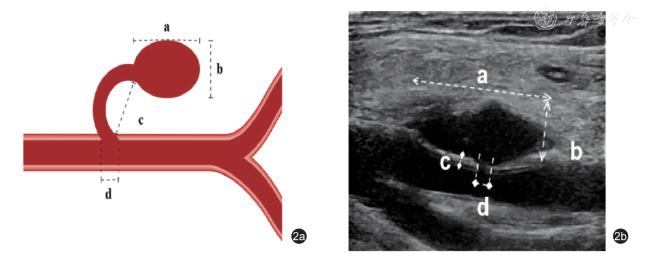

3.UGTI 治疗过程:在常规消毒铺巾后,确认合适的进针路径。使用凝血酶冻干粉溶于生理盐水中形成不同浓度的凝血酶冻干粉生理盐水混悬液。超声引导下采用5 ml 注射器穿刺假性动脉瘤,确认针尖到达瘤体内合适位置后,探头压迫假性动脉瘤,至瘤体体积缩小,瘤体内血流明显减少或无明显血流后,快速注入适量凝血酶冻干粉生理盐水混悬液。在注射过程中,通过二维超声及CDFI 实时动态监测瘤体内血栓形成情况。在瘤内形成血栓的同时,缓慢释放加压探头,直至假性动脉瘤完全回复且瘤内充满血栓,CDFI 确认瘤体内无血流后拔出注射器。术后再次确认瘤体内无血流信号,同时确认足背动脉搏动良好。记录凝血酶使用的剂量及浓度。术后嘱患者卧床休息1 ~2 d,避免患肢过度屈曲压迫瘤体,以免瘤体内的新鲜血栓被挤压出瘤腔进入动脉内,引起远端动脉栓塞。患者术后1、3、6 个月定期行超声随访复查(图3)。

图3 假性动脉瘤超声引导下注射凝血酶治疗术前及术后超声声像图。图a 为术前假性动脉瘤二维超声声像图;图b 为术前假性动脉瘤彩色多普勒血流图;图c 为术后瘤体内血栓形成二维超声声像图;图d 为术后瘤体内血栓形成彩色多普勒血流图